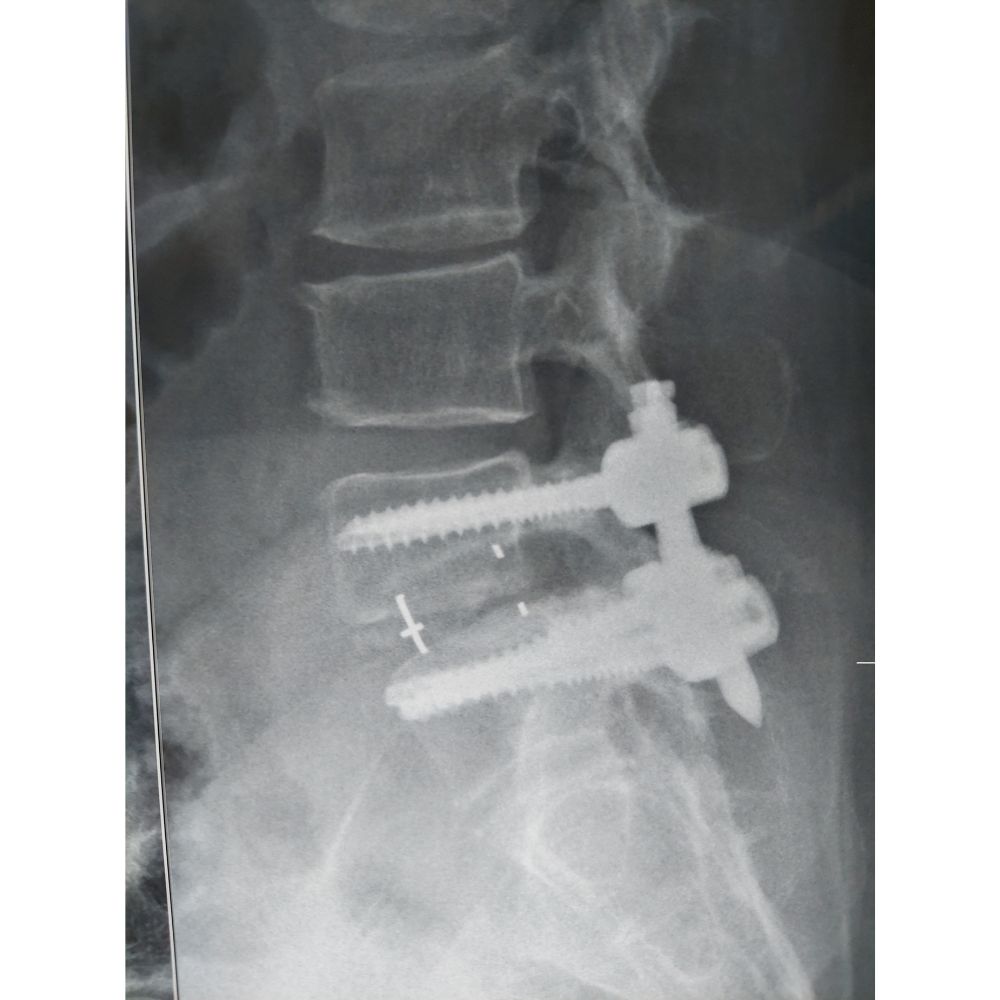

3. Disc Removal and Fusion: The damaged disc tissue is removed, and the intervertebral space is prepared for fusion. Bone graft material, often taken from the patient’s own body or a bone bank, is inserted into the disc space to promote fusion.

4. Implant Placement: Metal screws and rods may be inserted into the vertebrae to provide additional stability and support. These implants help maintain proper alignment and facilitate fusion of the affected vertebrae.

5. Closure: The incisions are closed with sutures or surgical staples, and a sterile dressing is applied to the surgical site.